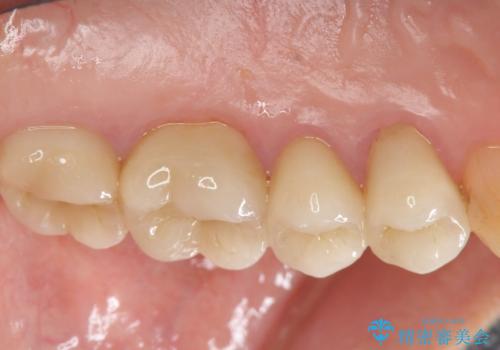

虫歯治療掲載症例数84件

最新 虫歯治療症例